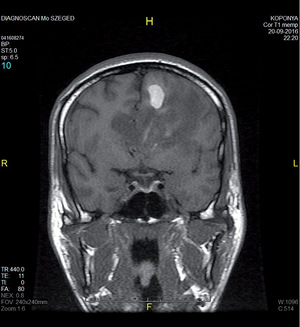

3.6.2. Daganatok: az agy (64–72. ábra)

- MRI: T2, FLAIR, T1/T1gad, DWI.